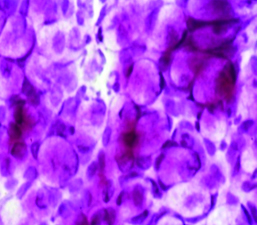

La citología de impresión (Fig. 16) permite identificar los cambios metaplásicos experimentados por la superficie epitelial conjuntival como consecuencia del ojo seco e identificar las características histológicas de las células mucosecretantes y de otras células que conforman a la superficie epitelial conjuntiva.

Figura 15: Proteinograma lagrimal

Figura 16: Citología de impresión

Permite diferenciar cuadros de ojo seco, de alergia, de disfunción de glándula de Meibomio, de toxicidad y realizar un correcto diagnóstico diferencial. Estudios comparativos con biopsia labial de pacientes portadores de Síndrome de Sjögren 22 le dan un gran valor diagnóstico de esa enfermedad.

Es de gran utilidad para diagnosticar disfunciones límbicas.

Estudios más complejos de laboratorio como la inmunohistoquímica (Fig. 17) sobre tejido conjuntival obtenido por biopsia permite el diagnóstico de certeza del penfigoide ocular cicatrizal al identificar depósitos de IgG, IgM y Complemento 3 en membrana basal.

Figura 17: Inmunohistoquímica